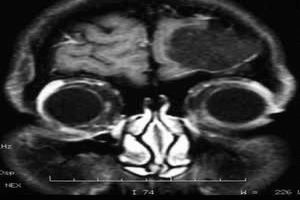

3.地中海貧血地中海貧血的男孩常伴低促性腺激素性性腺功能減退症,其GnRH分泌減少且無脈衝,嚴重病例(伴重度鐵質沉著症)的性腺功能障礙往往為不可逆性損害,而輕度病例往往可逆、鑑別可逆和不可逆性病變的方法之一是精確測量GnRH的脈衝特徵。MRI顯示,有些病人伴空泡蝶鞍綜合徵,垂體容量減小,垂體腺萎縮,垂體柄變薄,垂體和中腦有鐵質沉著。因此,病人應及早用HCG和(或)雄激素治療,並防止過度輸血引起的鐵質沉著。

2.應根據病情選擇相關的檢查下丘腦-垂體-性腺軸激素(血LH、FSH、T)及其他內分泌激素(如血T3、T4、TSH和GH等)水平測定,必要時行GH興奮試驗。染色體檢查用以除外染色體異常引起的性腺發育障礙,如Tumer綜合徵及Kline-Felter綜合徵。MRI或CT影像學檢查以便及時發現鞍區占位病變或其他疾患。

其他輔助檢查:染色體檢查用以除外染色體異常引起的性腺發育障礙,如Turmer綜合徵及Kline-Felter綜合徵。MRI或CT影像學檢查以便及時發現鞍區占位病變或其他疾患。X線測定骨齡,了解有無腺垂體功能減退。